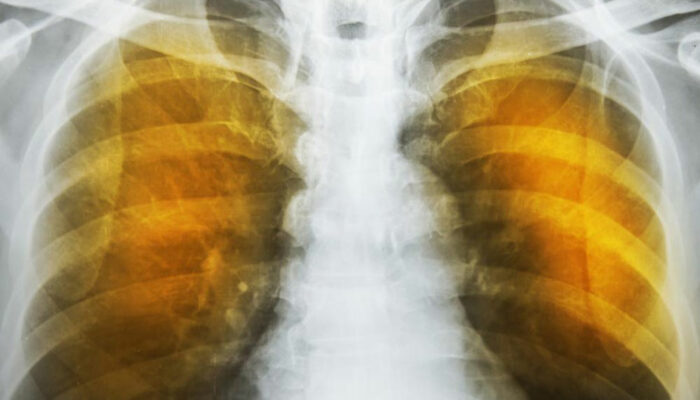

Emphysema is an oppressive respiratory disorder which results from the disintegration of the alveoli, i.e., the tissues where the interchange of gas with blood takes place. Destruction in any large scale will reduce the gas transfer area and the process of gas transfer itself, leading to oxygen starvation or hypoxia. When conventional treatment with bronchodilators, corticosteroids etc. have ceased to give relief, one has to resort to a method known as Long Term Oxygen Therapy or LTOT.

Another complication is the alveoli becoming weaker, and then starting to break. When this assumes larger scale, vacant spaces are formed called bullae. This reduces the gas transfer area as well as the capacity of the lung to expand. These are often have to be surgically removed to allow more space for the lung to expand. In the ultimate case, lung transplant becomes the only choice. Another scenario is a large-scale disintegration of alveoli that can cause pneumothorax, which is a condition in which the chest cavity is filled with air and the lungs collapse. This is a very serious condition if not fatal.